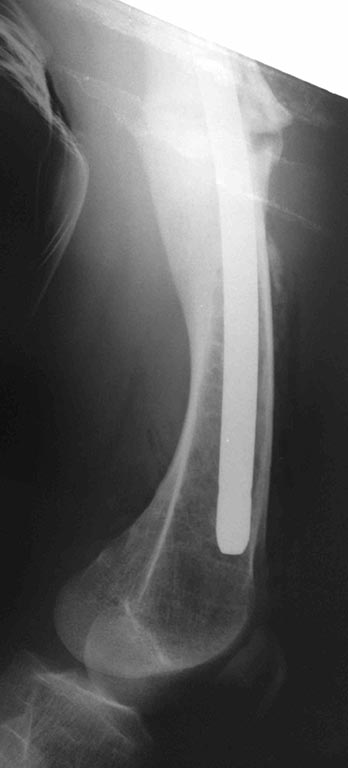

Как одна из ожидаемых проблем после выполнения вмешательства резкое

ограничение сгибания, так как в настоящее время надколенник ╚ уезжает ╩

с мыщелка при сгибании что, скорее всего, вызвало укорочение квадрицепса

и собственной связки надколенника. Может ли появиться

необходимость вмешательства на собственной связке и бугристости

одномоментно? Больной не настаивает на оперативном лечении. Родители же

согласны с необходимостью коррекции. Как один из вариантов не трогать

нам его совсем. Живёт же . Будем благодарны за соображения,

подсказки и опыт похожих ситуаций.